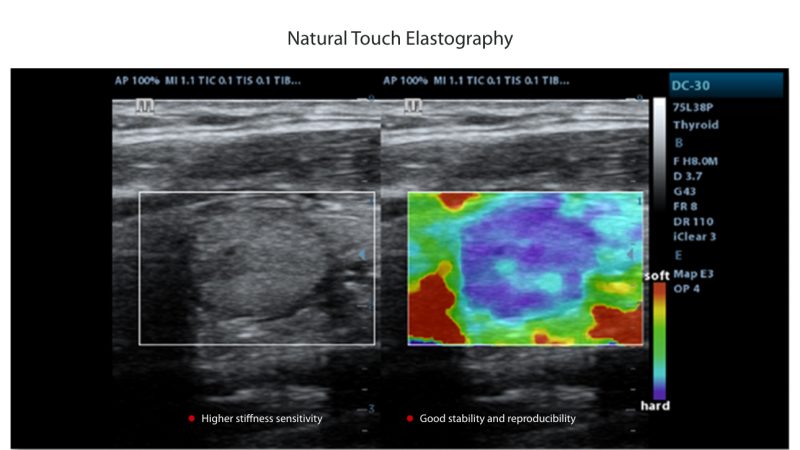

Standard ultrasound systems available today typically allow for a basic diagnosis but lack advanced functionality. Now, the DC-32 FullHD is the perfect answer for high-quality image performance, with 21.5 inches Full HD LED Monitor and advanced functions such as Auto IMT, iScape, Natural Touch Elastography, UWN Contrast Imaging and Tissue Doppler Imaging in General Imaging, and Smart OB, Smart face and iLive in OB.

Mindray DC 32 Full HD Ultrasound is a standard ultrasound system available today that typically allows for a basic diagnosis but lacks advanced functionality. Now, with the most competitive price in the industry, the DC-32 is the perfect answer for high-quality image performance, with added features such as Auto IMT, iScape, Natural Touch Elastography, UWN Contrast Imaging, and Tissue Doppler Imaging.

- Natural Touch Elastography, Based on Mindray’s latest patented technology, natural touch elastography reduces dependence on user operation technique, improving the operator’s reproducibility for higher clinical utility.